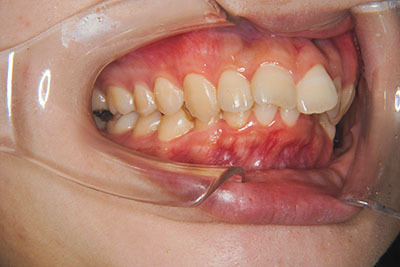

おとなの方でも矯正治療をあきらめないでください!

子供の頃に矯正治療を行う方が治療期間が短く済むというのは、確かですが、矯正治療は患者様の意識も重要です。

いくら歯が動き易くとも、本人がやる気でなければ効果は出ませんし、むし歯発生のリスクも高まります。おとなの方は顎の成長が終わっているため、治療の計画が立てやすいとも言えます。「もう大人だから…」とあきらめず、一度ご相談ください。